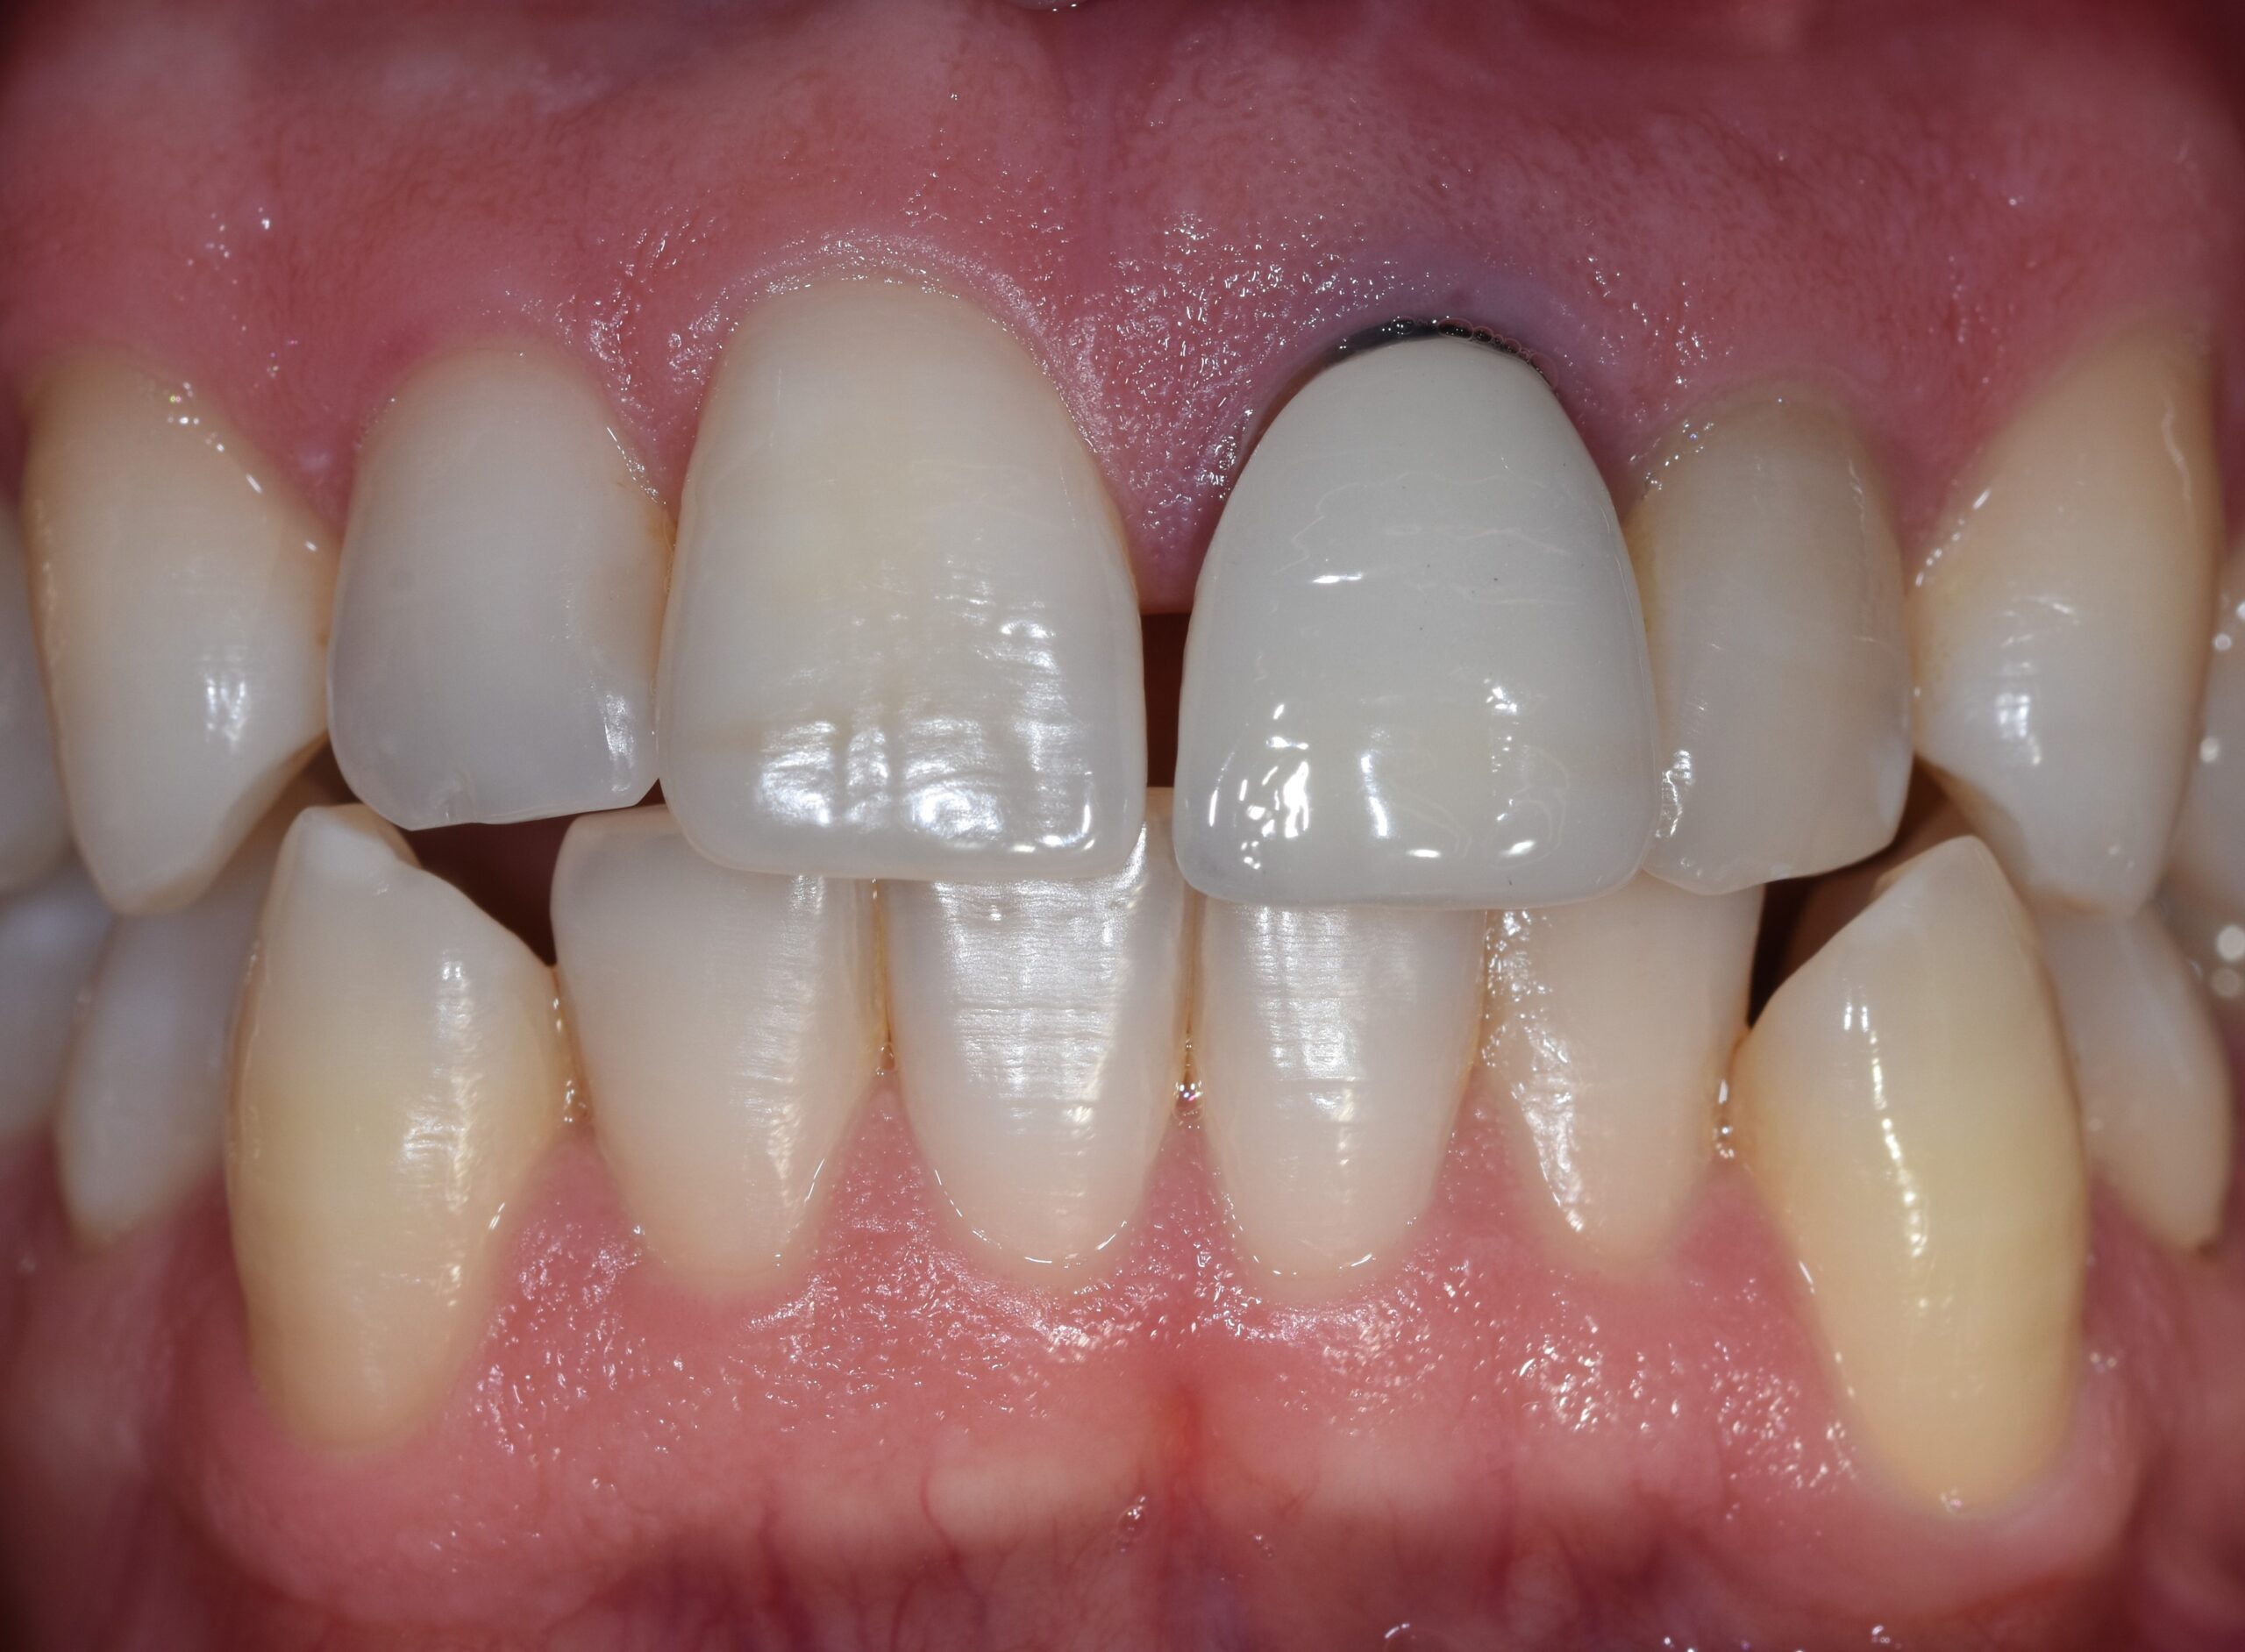

All’esame clinico, l’elemento presentava un restauro in metallo-ceramica e un profilo tissutale conservato nonostante una modesta recessione (Figura 1).

Il fenotipo gengivale appariva cheratinizzato con spessore di circa 1 mm e 6 mm in altezza. Il sondaggio parodontale era nei limiti della norma e in assenza di sanguinamento.

Al test di vitalità gli elementi 21 e 22 risultavano non vitali e all’esame radiografico endorale presentavano un’area di rarefazione periapicale molto estesa (Figura 2).

La corticale vestibolare era ben rappresentata e mantenuta in tutta la sua altezza.